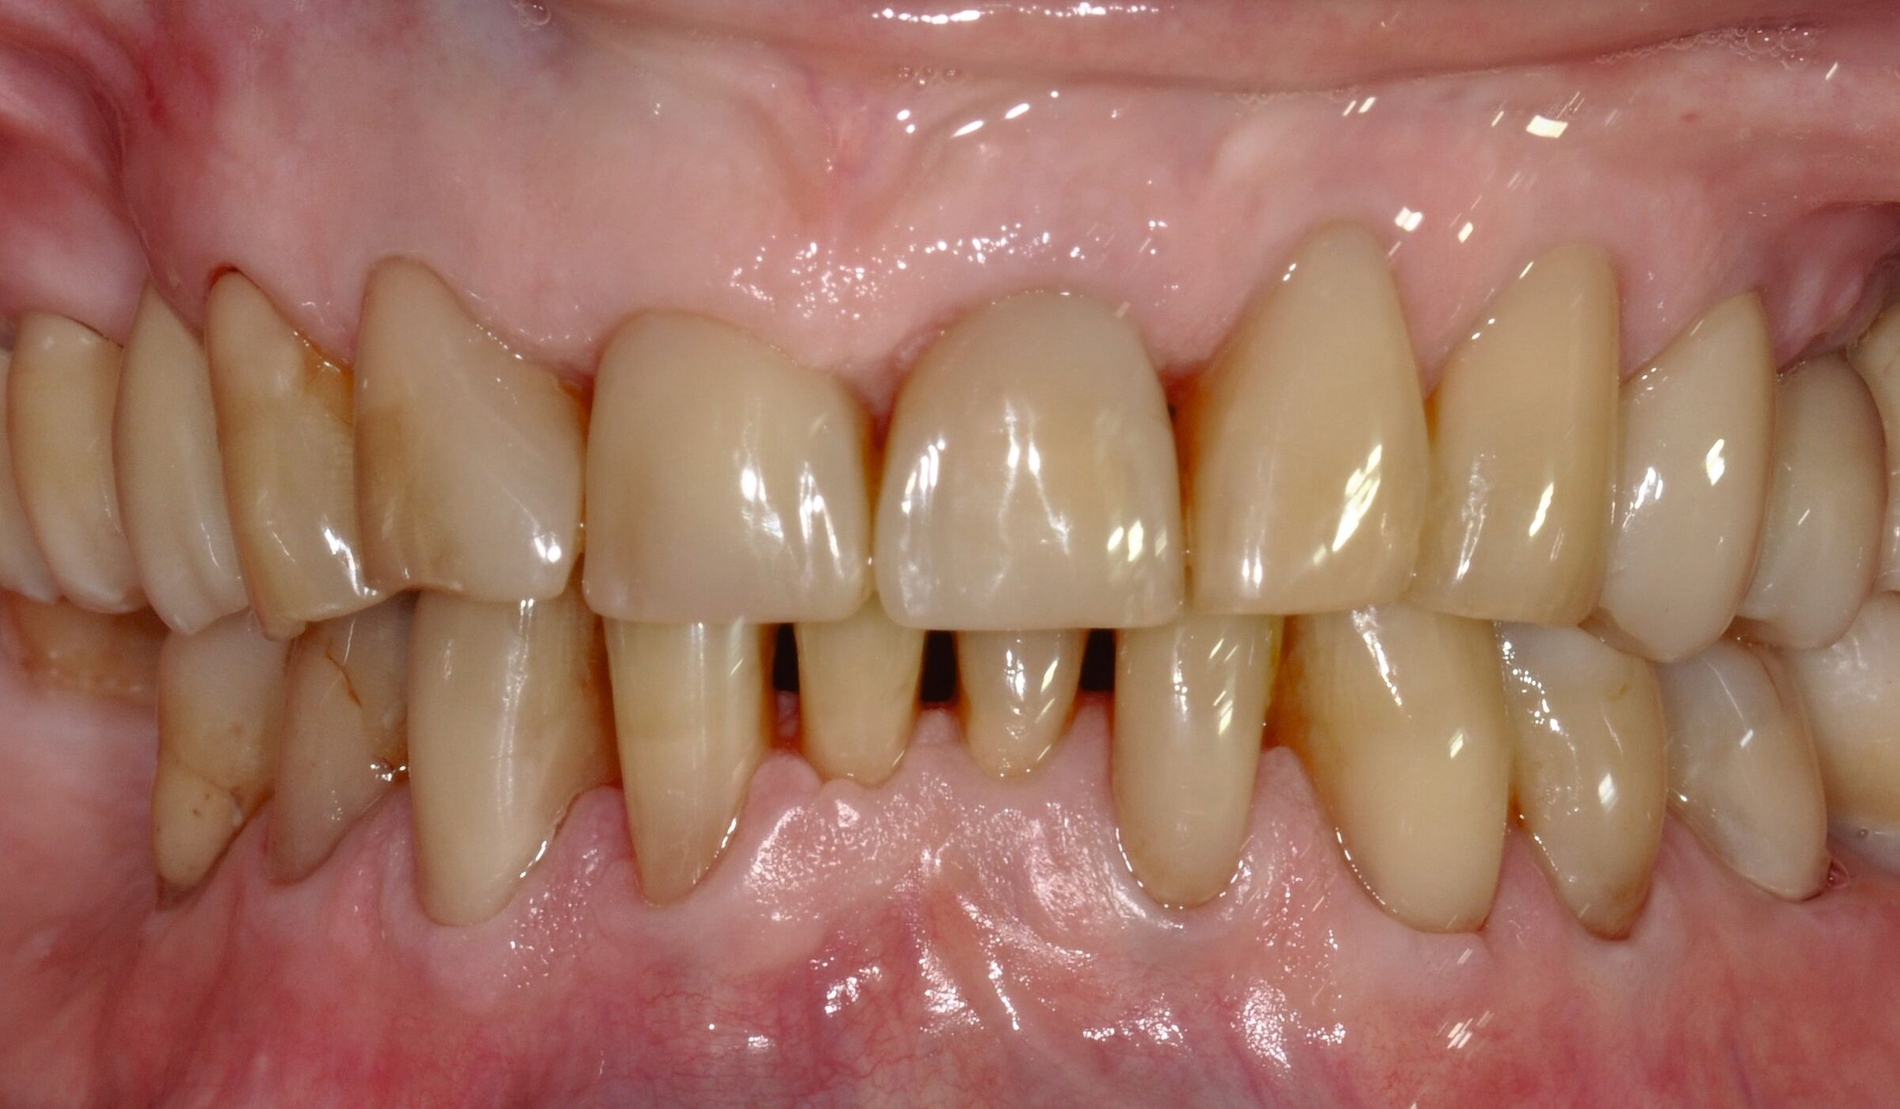

... mit Höckerersatz im Seitenzahnbereich

Für die Höckerüberkappung bedarf es eines ausreichend stabilen und abrasionsfesten Materials, das durch okklusale Kräfte belastet werden kann und die anatomische und funktionelle Rekonstruktion des Zahnes ermöglicht. Die Evidenz zur Verwendung von Kompositmaterialien bei Seitenzahnkavitäten mit Höckerersatz zeigt in mehreren Studien gute Überlebensraten [Deliperi et al., 2006; ElAziz et al., 2020; Fennis et al., 2014]. Van Nieuwenhuysen et al. [2003]berichtetenvon hohen Versagensraten sowohl bei Komposit- als auch bei Amalgamrestaurationen (30,4 Prozent beziehungsweise 28,1 Prozent). Diese Daten sind jedoch aufgrund der Verwendung älterer Kompositmaterialien als veraltet zu werten.

MERKE: Moderne Kompositmaterialien sind leistungsfähig und entsprechen den Prinzipien der minimalinvasiven Zahnmedizin. Insofern ist die Höckerrestauration mittels Komposit möglich (Abbildung 2).

Die Gruppe hat mit starkem Konsens die Empfehlung ausgesprochen, dass für Höcker-ersetzende Restaurationen insbesondere bei spezifischen Einflussfaktoren auf Zahn-, Mund- und Patientenebene (zum Beispiel eingeschränkte Compliance, schlechte Zugänglichkeit, komplexe funktionelle Rehabilitation) der Einsatz von indirekten Kompositrestaurationen erwogen werden kann.